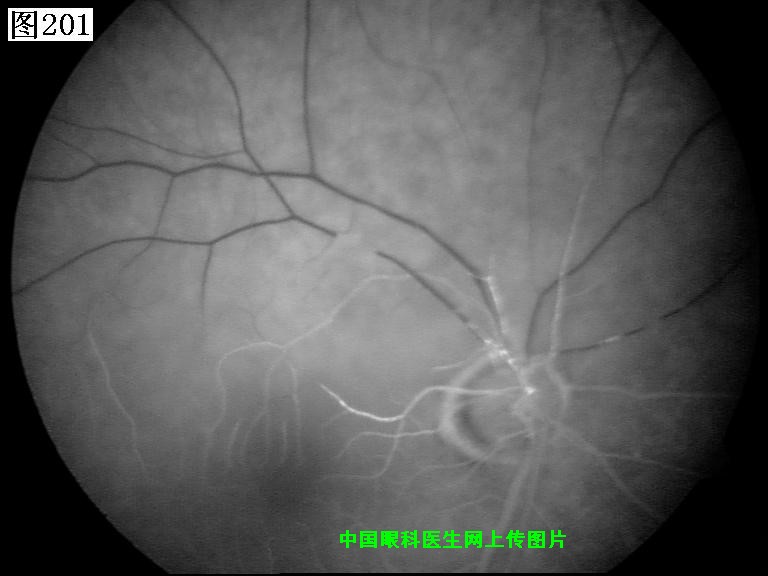

201 202 203 204